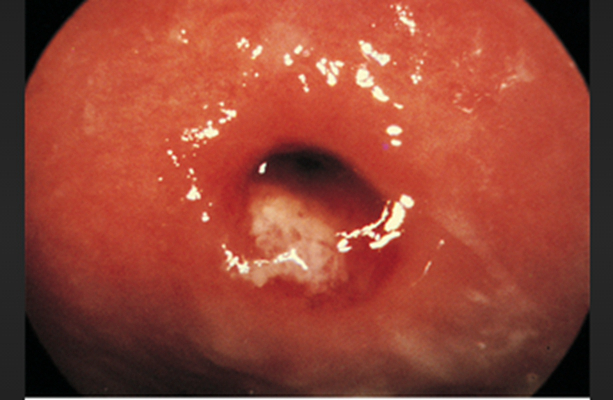

淋病圖片

淋病的症狀 (7)

淋病的症狀 (8)

淋病的症狀 (9)

淋病的症狀 (47)

淋病的症狀 (48)

淋病的症狀 (49)

淋病的症狀 (5)

淋病的症狀 (50)

淋病的症狀 (51)

淋病的症狀 (52)

淋病的症狀 (53)

淋病的症狀 (54)

淋病的症狀 (55)

淋病的症狀 (56)

淋病的症狀 (6)

淋病的症狀 (40)

淋病的症狀 (41)

淋病的症狀 (42)

淋病的症狀 (43)

淋病的症狀 (44)